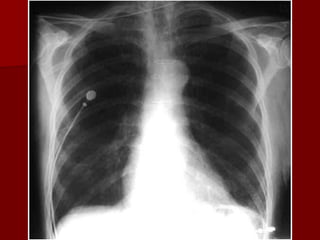

Penetration

SEE THE NODULE ON THE

PREVIOUS FILM